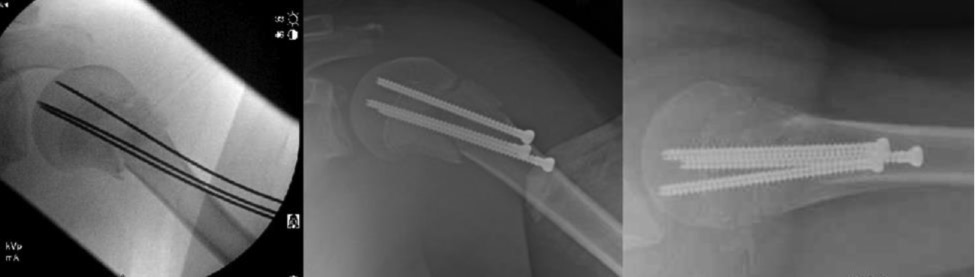

Definitive Fixation with Cannulated Screws

Initially, we treated all patients with smooth pins, yet concerns of pin site irritation and fracture displacement have led to using cannulated screws as preferred fixation. We use 4.5 mm cannulated screws and place the guide pins with similar techniques as described above. Once three guide pins are placed, we carefully drill (using drill sleeve) the near cortex of the humeral shaft and place fully threaded screws into the metaphysis of the humeral head (Figures 12 and 13). Although we don’t intend to remove, theoretically, fully threaded screws as opposed to partially threaded screws, would be easier to remove if ever indicated at a later date.

Figure 12. A 14-year-old boy from an ATV accident with multiple fractures.

jposna2023703_fig12.jpg

Figure 13. The proximal humerus was treated with closed reduction and screw fixation. At 1 year, he has had good healing and has no complaints of shoulder pain.

jposna2023703_fig13.jpg